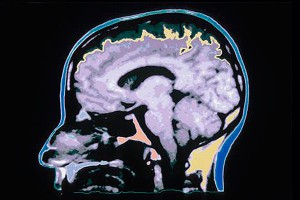

Томские ученые воссоздали мозг человека17 августа 2015, понедельник, 17:45 – БРЯНСК.RU | | Версия для печати Как сообщает официальный сайт Томского государственного университета, проектом занимается международная лаборатория Центра превосходства "Интеллектуальные технические системы". Ученые приблизилась к созданию искусственного интеллекта, способного не только приобретать опыт, но и "забывать" информацию, теряющую актуальность."Сначала были построены математическая и компьютерная модели мозга человека. После этого был сконструирован радиоэлектронный прибор, содержащий перцептроны. Он способен обрабатывать разноплановую информацию (видео, звук и т.д.). Сейчас идет работа по созданию основной системы робототехнического комплекса, который представляет собой интеллектуальный центр управления", – рассказал руководитель лаборатории профессор Владимир Сырямкин. Как уверяют ученые, данная физическая модель способна к самообучению и накоплению жизненного опыта. Искусственный носитель естественного интеллекта воспринимает внешние раздражители, такие как свет и звук. Методом проб и ошибок он пытается найти решение, которое поможет избежать влияния этого раздражителя. Например, при воздействии яркого источника света он сначала попытается отвернуться, если это не помогает, то отодвинуться от него. До тех пор, пока мозг не отыщет правильное решение, его нейроны (перцептроны) будут находиться в возбужденном состоянии. Когда искусственный разум это решение найдет, он его запомнит и станет использовать в сходных жизненных ситуациях. "В конечном варианте мы хотим достичь максимальной приближенности искусственного разума к биологической модели головного мозга, – подчеркнул профессор Сырямкин. – Поэтому в скором времени в наш проект вольются специалисты из других областей – биологи и психологи. Ведь искусственный интеллект должен не только уметь самостоятельно мыслить, но и различать, что такое хорошо и что такое плохо с точки зрения этики". По словам исследователей, возможности использования созданного ими искусственного интеллекта практически безграничны. Однако основной упор будет сделан на поиск методов лечения болезней, связанных с нарушением нейронных связей в мозге, различных видов амнезий, а также болезней Альцгеймера и Паркинсона. С помощью искусственной модели ученые смогут тестировать способы лечения. Источник: